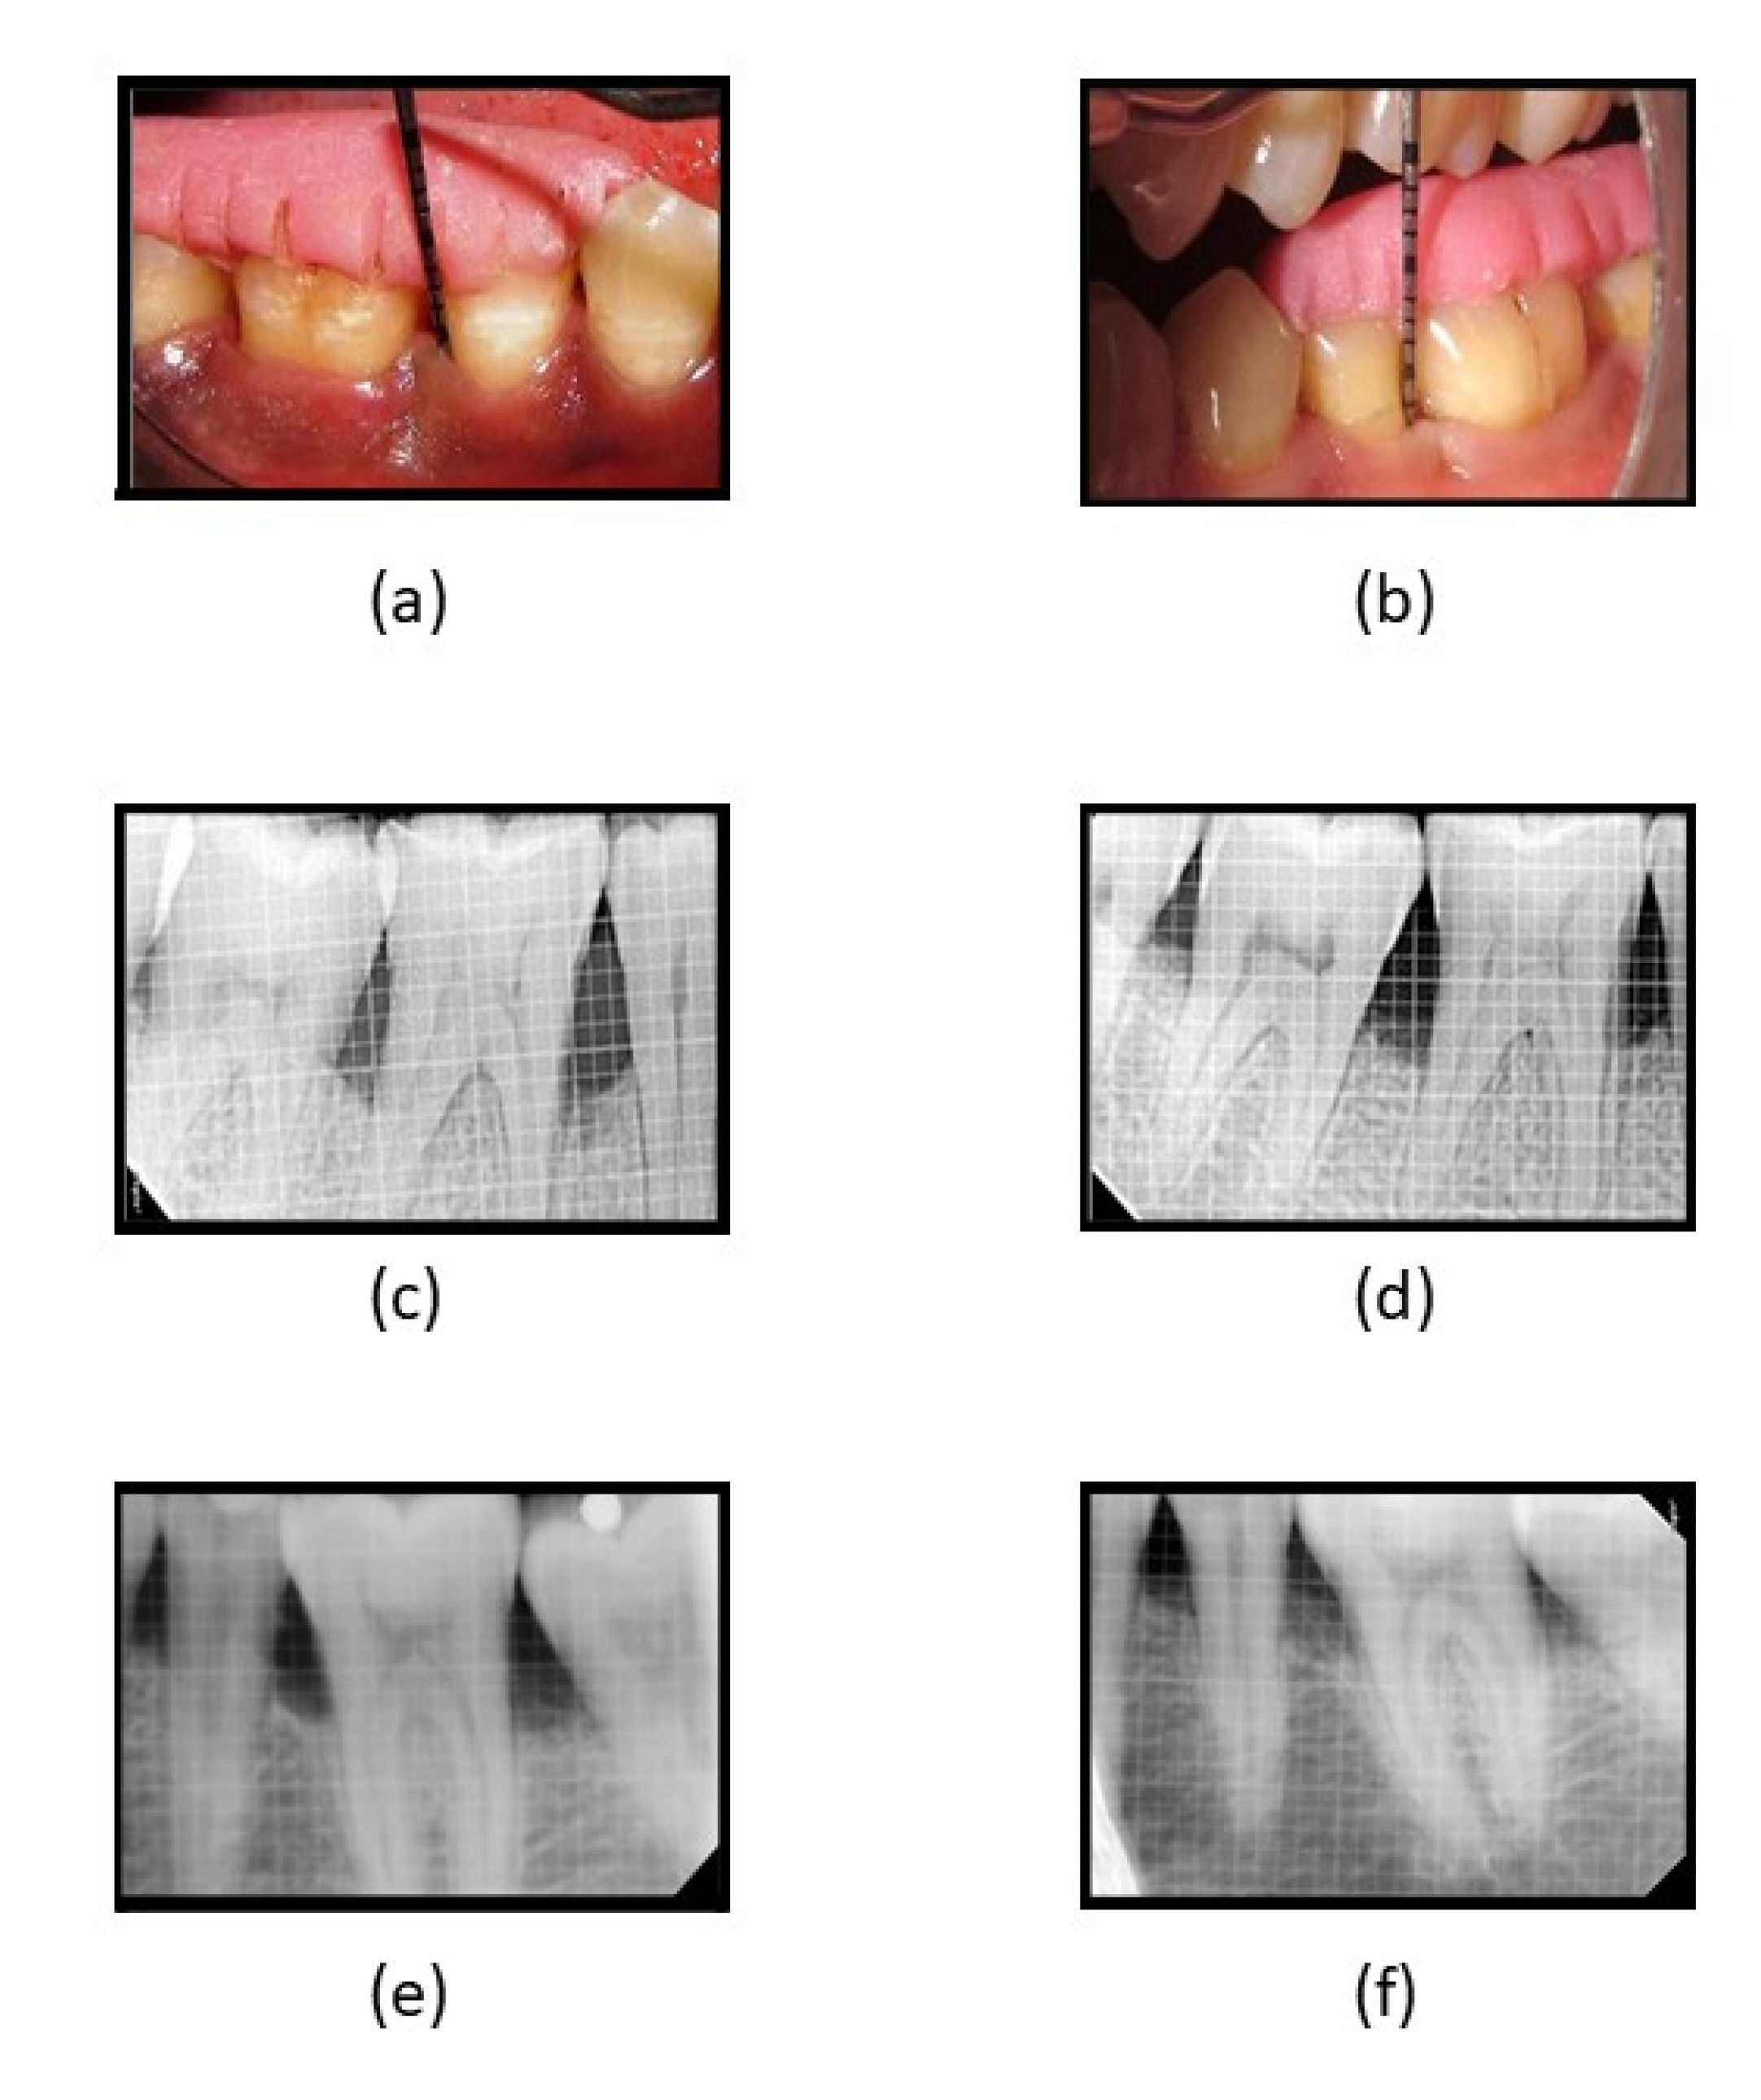

Clinically, in its osteogenic effectiveness in periodontal intra-bony defects management, the mean age of the participants recruited was 43.75 (5.638) years, with a higher percentage of females (60%, n = 24) (Table 3). Statistically significantly lower plaque index scores were observed in both groups at 6 and 9 months as compared to baseline (p < 0.05), while significantly lower scores in all other clinical parameters were observed at all three-time intervals when compared to baseline in both groups. Intergroup analyses showed significantly lower scores were observed in the GCF group at 3 and 6 months, while both groups were comparable at 9 months (Table 4). A statistically significant reduction was observed in radiographic parameters at 9 months in both groups (p < 0.05). A higher defect fill was seen in the fucoidan-chitosan group at 9 months, with lower CEJ-base measurement (Table 5). The clinical and radiographic improvement is shown in Figure 5.

Figure 5. (a) Reduction in PPD at 3 months in fucoidan-chitosan group; (b) reduction in PPD at 6 months in fucoidan-chitosan group; (c) RVG image of intra-bony defect at baseline in fucoidan-chitosan group; (d) RVG image of improvement in intra-bony defect at 9 months in fucoidan-chitosan group; (e) RVG image of intra-bony defect at baseline in CGF group; (f) RVG image of intra-bony defect at 9 months in CGF group.